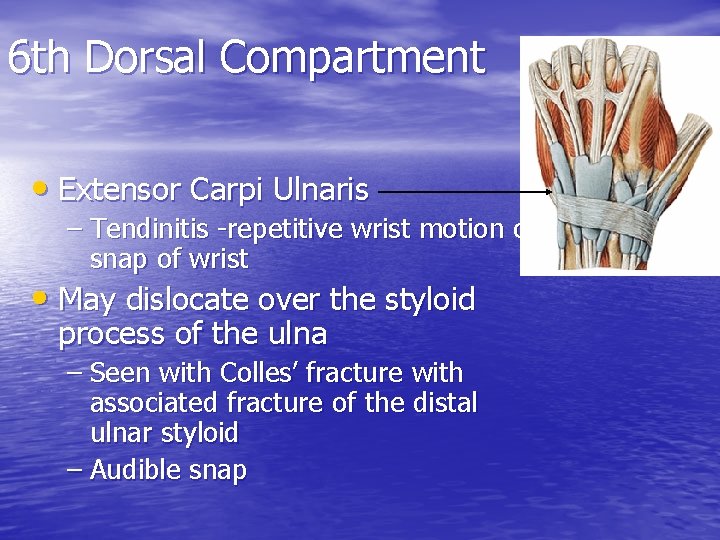

6 th Dorsal Compartment • Extensor Carpi Ulnaris – Tendinitis -repetitive wrist motion or snap of wrist • May dislocate over the styloid process of the ulna – Seen with Colles’ fracture with associated fracture of the distal ulnar styloid – Audible snap

Extensor Carpi Ulnaris Tenosynovitis and Subluxation • 6 th Dorsal Compartment • Second most common site of tenosynovitis (after De. Quervain’s) • Common in racket and rowing sports • Pain and tenderness with ulnar deviation • Suspect subluxation when clicking on ulnar side of forearm